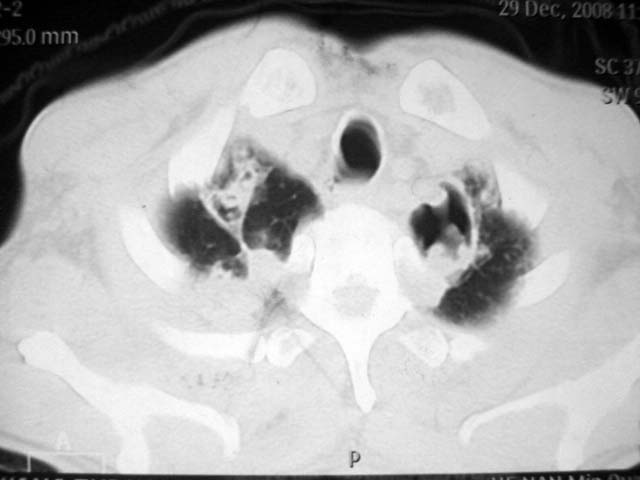

男,52岁,发热2月,糖尿病史。

抗结核治疗irpz方案,血糖未治疗,空腹15.9左右。症状无好转,左胸痛。

2、双肺见多发片状及结节状高密度影,大多数病灶中心均见“空泡征”。

3、纵隔内淋巴结肿大。

结果:两肺继发性肺结核并曲霉菌感染。